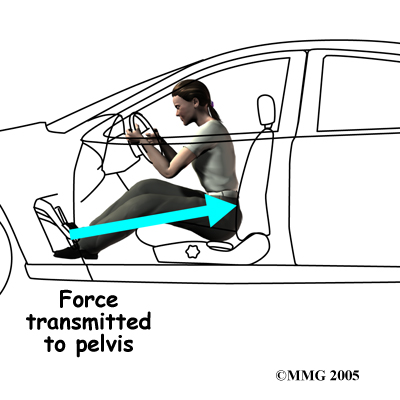

Injury to the SI joint is thought to be a common cause of pain. Injury can occur during an automobile accident. One common pattern of injury occurs when the driver of a vehicle places one foot on the brake before a collision. The through the foot on the brake is transmitted to the pelvis causing a twisting motion to this side of the pelvis. This can injure the SI joint on that side resulting in pain. A similar mechanism occurs with a fall on one buttock. The force again causes a twisting motion to the pelvis and may injure the ligaments around the joint.